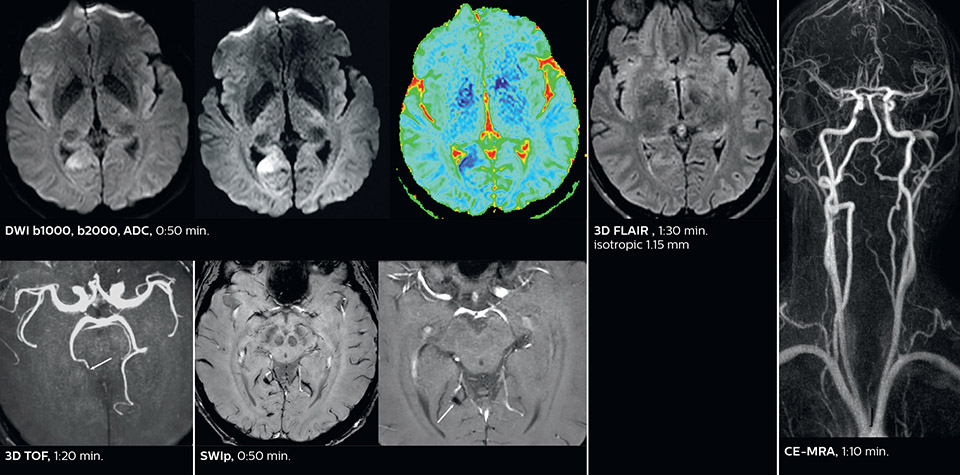

Dr. Savatovsky appreciates the improvements and flexibility that Elition with Compressed SENSE and MultiBand SENSE provides, particularly for stroke patients. “For stroke, it allows us to cut about 5 minutes off of our stroke protocol, or to keep the same acquisition time and get more insights.” The ability to perform more sequences can help in making a swift and confident diagnosis. “For example, our stroke cases usually include the regular sequences that every center does (b1000 diffusion, FLAIR, time-of-flight angiography), but we also image supra aortic vessels, and we can replace a gradient echo sequence with a fast 50-second susceptibility-weighted sequence, and all of this doesn’t add much time. because all the regular sequences are accelerated on Elition.” “The time savings with Compressed SENSE and MultiBand SENSE make it easier to add sequences to give us additional insights. Depending on the context and the first results, we might add a DSC perfusion to assess the ischemic penumbra, an ASL perfusion to help find an alternative cause in case of normal diffusion, or add a high-resolution T1 sequence for a stroke patient, to quickly assess wall imaging in emergency cases. The additional sequences can help improve patient management, because we can already consider some alternative diagnoses if the morphological MRI is normal.”

Using MultiBand SENSE allowed the staff to improve their diffusion quality. “Our diffusion sequence was already fast before, about 40 seconds. Now with Elition, it still lasts 40 seconds, but we improved the spatial resolution by 0.2 mm and use high b-values to be more sensitive to visualize changes related to acute stroke,” says Dr. Savatovsky. “We now also developed a high resolution DTI sequence (1.3 x 1.3 x 2 mm) that can be reformatted and takes 2 to 5 minutes depending on the coverage. We use it every time we have a doubt, or when we expect the diffusion to be abnormal but don’t see that on the fast sequence. We occasionally spot small ischemic infarctions that would not have been visible with the regular diffusion sequence.”

This is an example of acute ischemic stroke with distal occlusion of the right posterior cerebral artery. Note the improved visibility of the ischemic territory on the diffusion weighted image with high b-value. The 3D FLAIR shows a distal PCA occlusion. The fast SWIp depicts the thrombus on the isolated second echo image. The total scan time (including SmartBrain, preparations and a fast 3D T1w TSE Gd) is 8:00 minutes.

In this patient with acute right motor deficit and aphasia, the b2000 diffusion weighted image is normal. The SWIp image demonstrates more prominent veins in the right hemisphere, which could reflect increased deoxyhemoglobin contents. Fast ASL shows low CBF regions in the left frontal lobe. A follow-up ASL after one hour demonstrates high CBF values in the same area. The final diagnosis was migraine with aura.